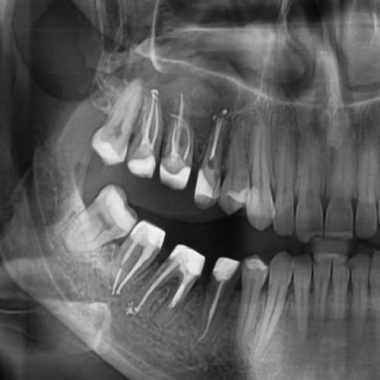

Червоним кольором підведені коріння зуба в гайморової пазусі.

- КТ – забезпечує саму точну діагностику, дозволяє виявити наявність чужорідного тіла та інших запальних процесів, масштаби ураження слизової оболонки порожнини носа та кількість гною.

- Рентгенографія верхньощелепних пазух – на знімках відмінно видні всі ущільнення, гнійні освіти та інші дефекти.В даному випадку також знадобиться діагностика та консультація лікаря-хірурга, комплексний огляд допоможе виявити проблему і призначити лікування.